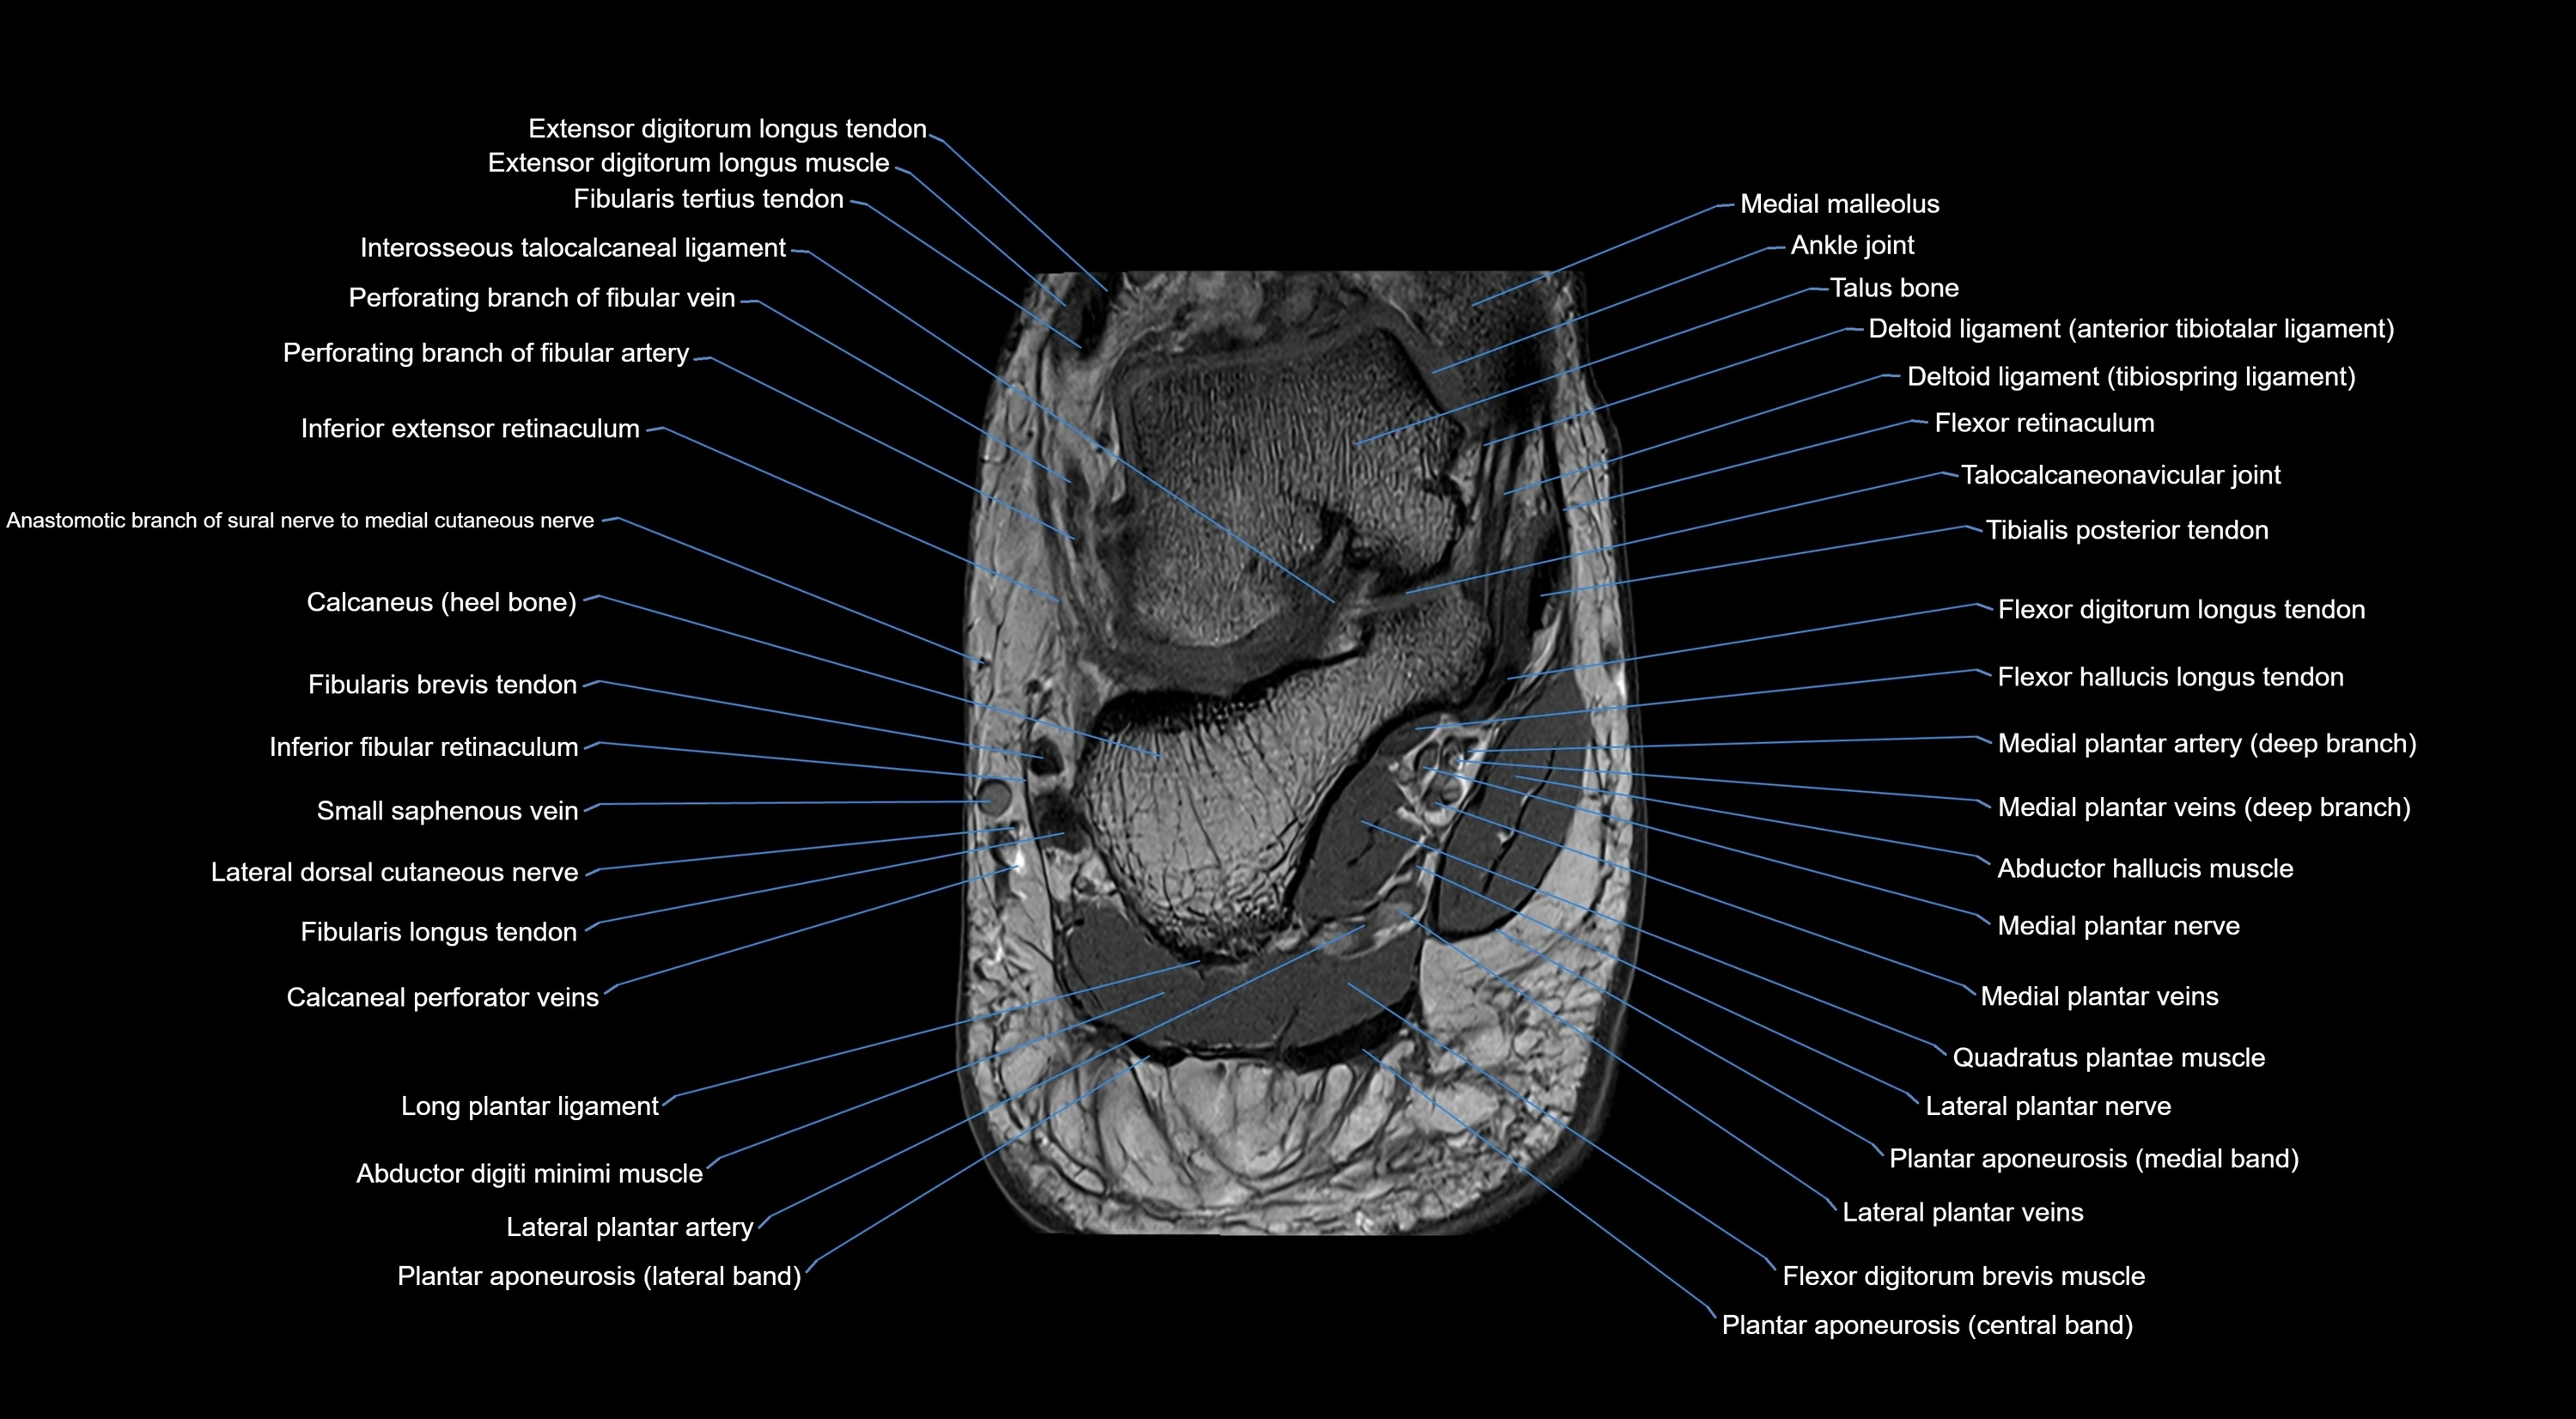

MRI image